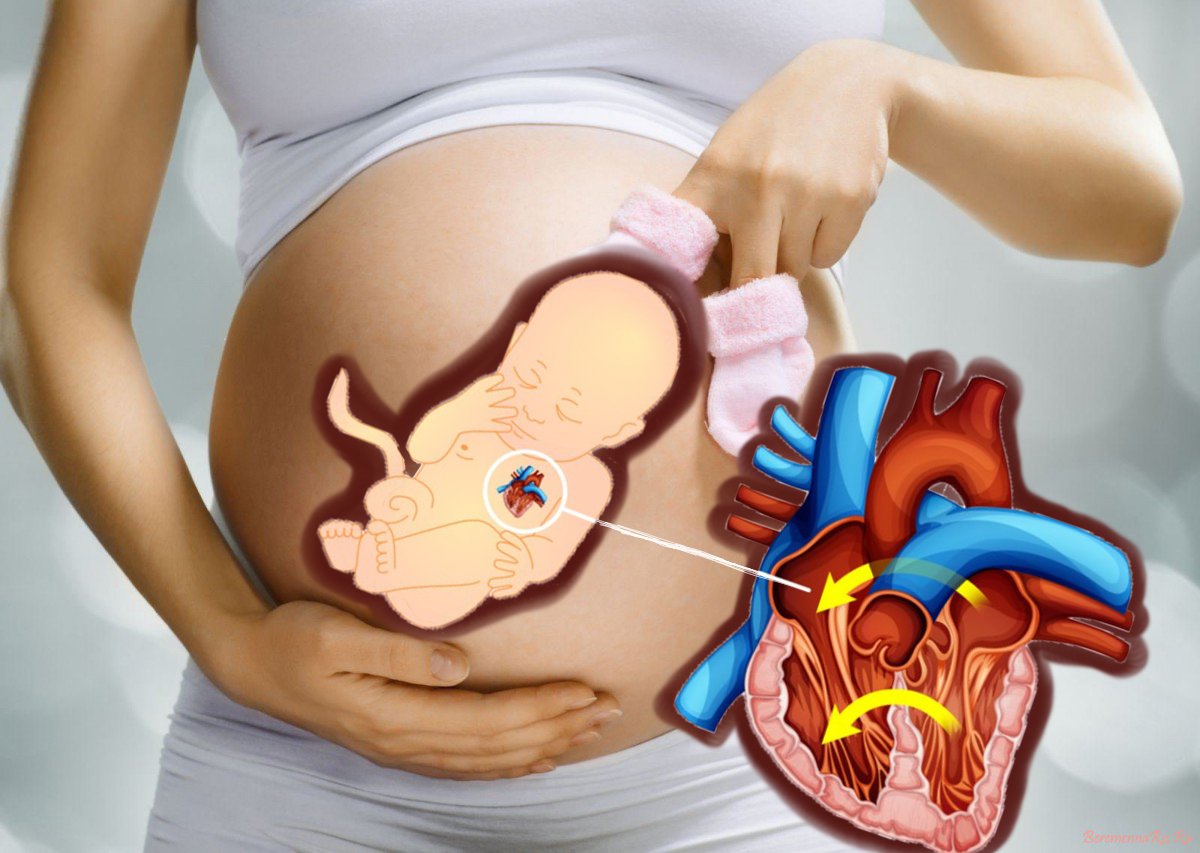

Фотографии и информация о приобретенных пороках сердца